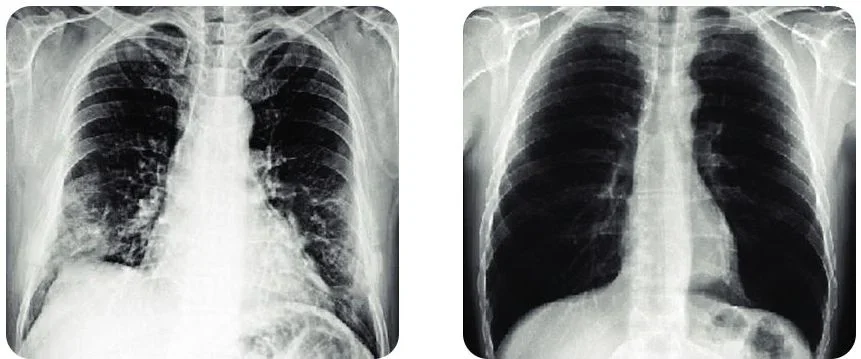

I've been drinking this tea for about 5 weeks and I'm just thrilled with the result, the picture below is the best proof of the change.

Like ·Reply ·

2 · 2 h